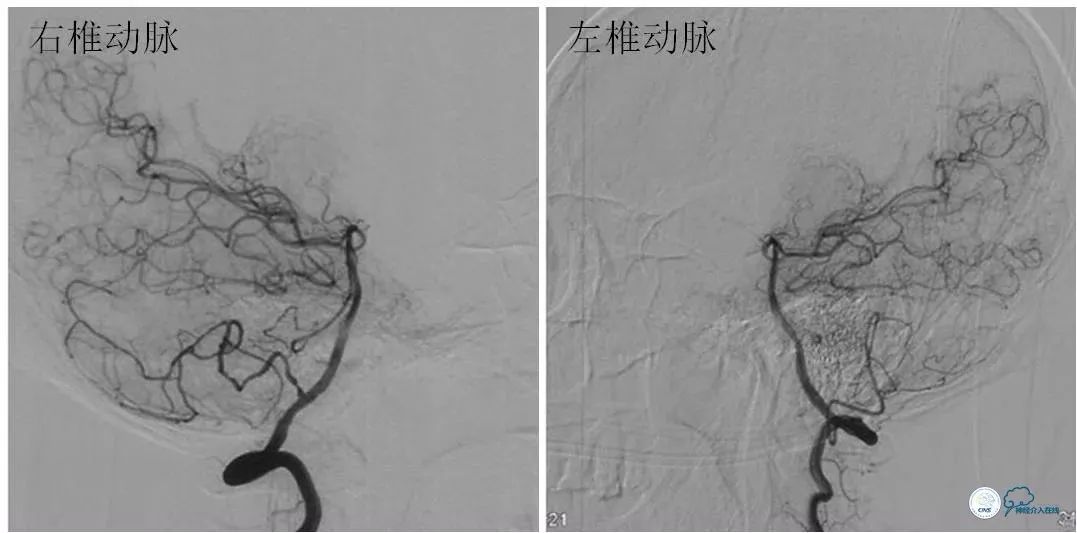

全麻下右股动脉入路,8F导引导管至左颈总动脉末端,将6F Navien导管送至左颈内动脉C1段以远,造影示左颈内动脉C6-7段长段狭窄,狭窄率约90%,长度约10mm(图7)。

图7

路径图下沿Navien导管送入Echelon 10微导管携Synchro微导丝(0.014″,200cm)尝试过狭窄段未成功(图8)。

图8